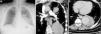

A 54-year-old man diagnosed with Behçet's Disease (BD) 5 years previously at another hospital was admitted to our center with massive hemoptysis. The chest X-ray showed bilobular, smooth edged opacity localized in the left hilar and paracardiac region that not conceal heart contours (Fig. 1a, arrow). Computerized tomography pulmonary angiography showed 2 lesions originating from the upper and lower branches of the left pulmonary artery, their central zones filled with contrast material, at early phase of imaging (Fig. 1b, arrow). Contrast filling was enhanced at late phase of the imaging (Fig. 1c, asterisk). The periphery of the lower lesion was less opaque, with small air bubbles (Fig. 1c, arrow). The signs suggested thrombosed pseudoaneurysms ruptured into the bronchus. The patient was diagnosed with a rupture of pulmonary artery aneurysm (PAA) and high dose glucocorticoid and cyclophosphamide pulse therapy was started.

The chest X-ray showed opacity localized in the left hilar and paracardiac region (a, arrow). Computerized tomography pulmonary angiography (CTPA) showed 2 lesions, originating from upper and lower branches of the left pulmonary artery (b, arrow). Contrast filling was enhanced at late phase of imaging (c, asterisk), with small air bubbles at the periphery of the lower lesion (c, arrow).